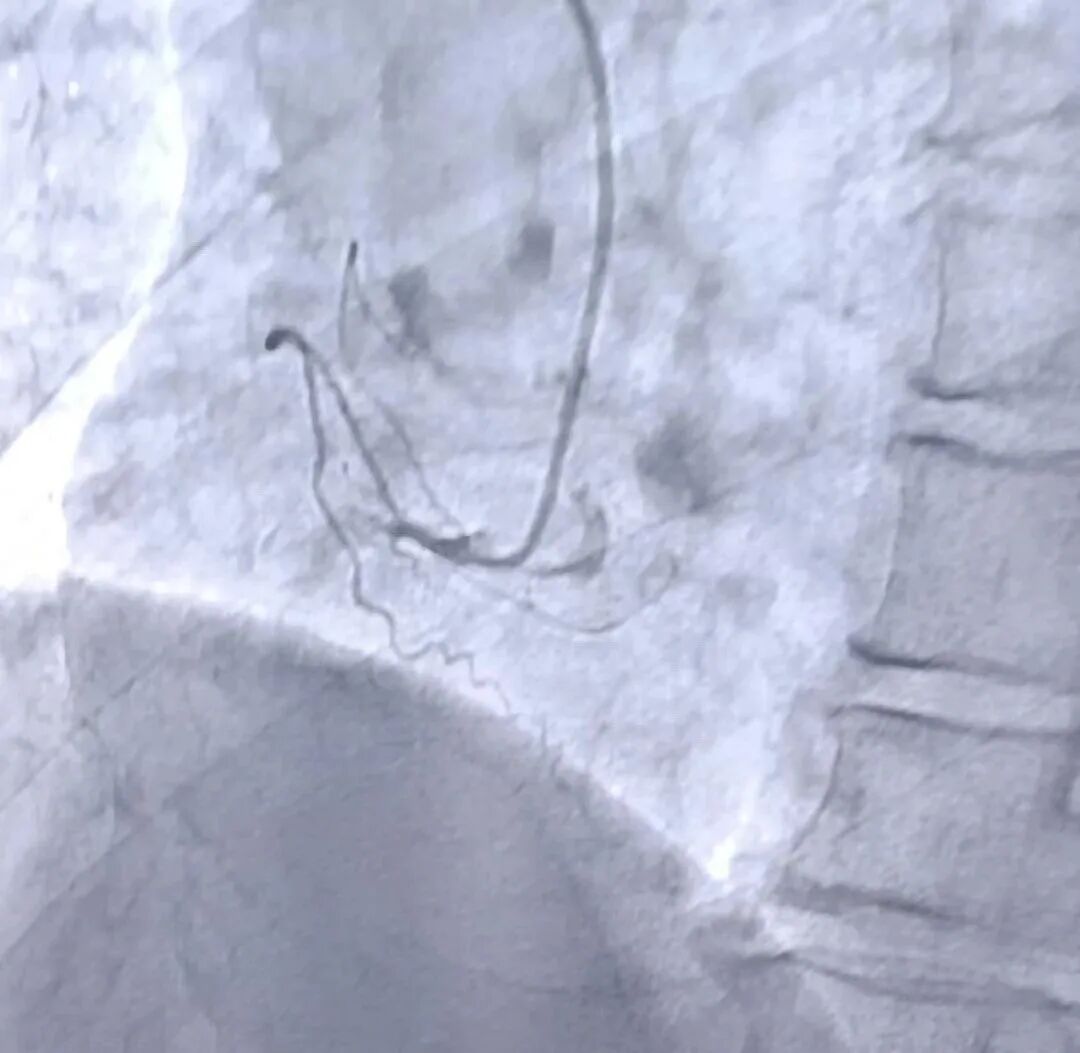

(术前造影图像)

当时这位患者因突发胸痛被紧急送往我院,经诊断为急性心肌梗死。时间就是生命,心血管内科医护团队迅速启动绿色通道,为患者进行了冠状动脉造影术,并成功实施了介入手术,开通了堵塞的血管。术后,患者恢复良好,经过一段时间的住院治疗,最终痊愈出院。

冠状动脉造影术是诊断冠心病的“金标准”,通过向冠状动脉内注入造影剂,医生可以清晰地看到血管的狭窄或堵塞情况。对于急性心肌梗死患者,冠状动脉造影术不仅是诊断手段,更是治疗的关键步骤。